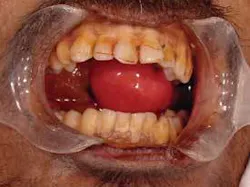

Forensic photography is an element of crime scene investigation that requires the individual to “have a good grasp of photographic terminology and the skills for operating basic camera equipment.”5 Both still and digital photography are accepted methods; however, according to C. Michael Bowers, “Good photographic results are a minimum standard for every competent law enforcement agency. Poor crime scene photography will impact the quality and outcome of every forensic case and reflect negatively on everyone involved.”6 Given these specific parameters, the dental hygienist interested in this aspect of forensics should seek enrollment in photography courses and perhaps turn a popular hobby into a specialty that can be used to help identify the deceased or the perpetrator of a crime. Samples of forensic photography are shown in Figures 2 and 3.